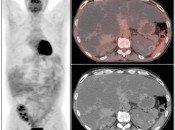

The normal liver demonstrates diffuse FDG uptake (typically greater than or equal to the spleen).

Many readers consider the uptake in the liver to represent the “background metabolic activity” for an exam.

For assessment of many lesions found in the body, the metabolic activity of the liver serves as the reference threshold by which to decide what is benign (uptake < liver) and what is malignant (uptake > liver).

Focal increased FDG uptake in the liver is always highly suspicious for malignancy. Very commonly, these malignant lesions may be poorly delineated on the co-registered CT images due to the lack of intravenous contrast administration.

Non-avid, low attenuation liver lesions are almost always benign (usually representing cysts, hemangiomas or fully treated malignant lesions), although some hepatocellular carcinomas can demonstrate only very mild metabolic activity.